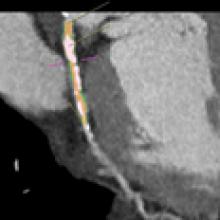

There has been growing clinical evidence to show computed tomography (CT) coronary artery calcium scoring shows a close correlation with a person’s long-term risk for heart disease. This data convinced the American College of Cardiology (ACC) to include CT calcium scoring in its revised guidelines for prevention and cholesterol released last fall. In addition, the ACC highlighted the evidence for CT calcium scoring as a late breaking session at its 63rd Annual Scientific Session in March.